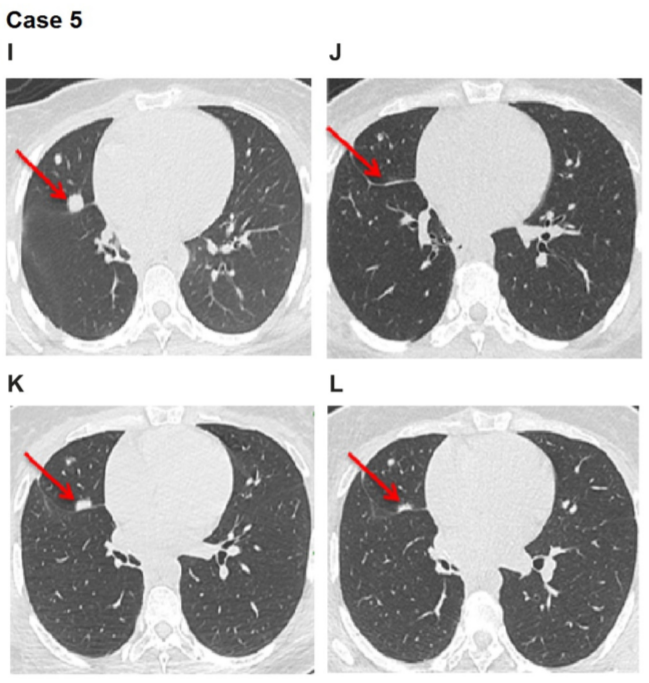

案例5

患者5为34岁女性,非洲人,从不吸烟,于2016年12月被诊断为侵袭性粘液性肺腺癌。肿瘤突变负荷极低(1.26 mutations/mb),没有PD-L1表达,双侧肺转移。

检测结果显示患者有SDC4-NRG1融合。患者直接使用阿法替尼40毫克/天作为1线治疗,使用6周后,评估为PR。

5个月后肺部出现进展,但治疗并未就此结束,医生选择给患者增加阿法替尼剂量为50毫克/天,惊喜地再次观察到PR,持续6个月。随后患者接受了其他疗法。

I:2018年1月治疗前的评估;J:2018年5月,阿法替尼治疗达PR的评估;K:2018年6月,疾病进展的评估;L:2018年8月提高剂量到50毫克/天达PR的评估

从侵袭性非粘液性肺腺癌患者中的结果来看,无论患者是否有吸烟史,阿法替尼在1线或3线使用,均有疗效。

值得注意的是,患者4无吸烟史,其PR时间长达18个月。另一个有趣的点是,患者5使用阿法替尼PR持续5个月后,出现进展,增加阿法替尼剂量,患者又继续PR长达6个月,即患者前后PR达到了11个月的时间。